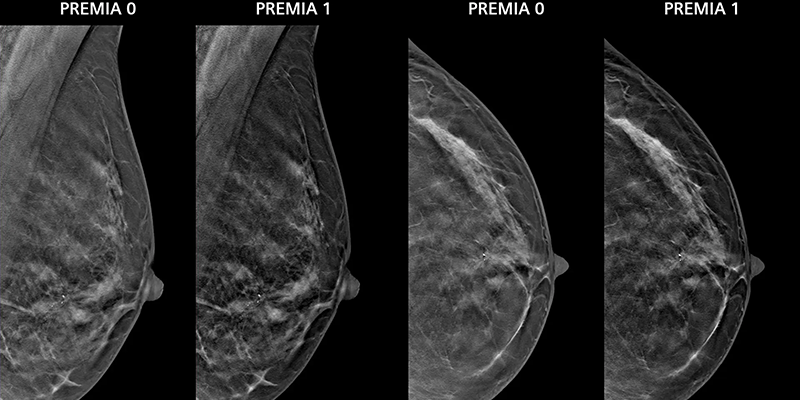

Главное обновление — новый метод реконструкции изображения ClearCEM, повышающий видимость очагов поражения, особенно в плотной молочной железе. ClearCEM обеспечивает более равномерный фон и высокую контрастную дифференциацию, что позволяет снизить необходимость в дополнительной визуализации или повторной биопсии.

«Качество изображения с ClearCEM исключительное, даже в плотной ткани молочной железы», — отметила радиолог из Envision Healthcare Дианна Джорджиан-Смит, участвовавшая в клинических оценках новой методики.